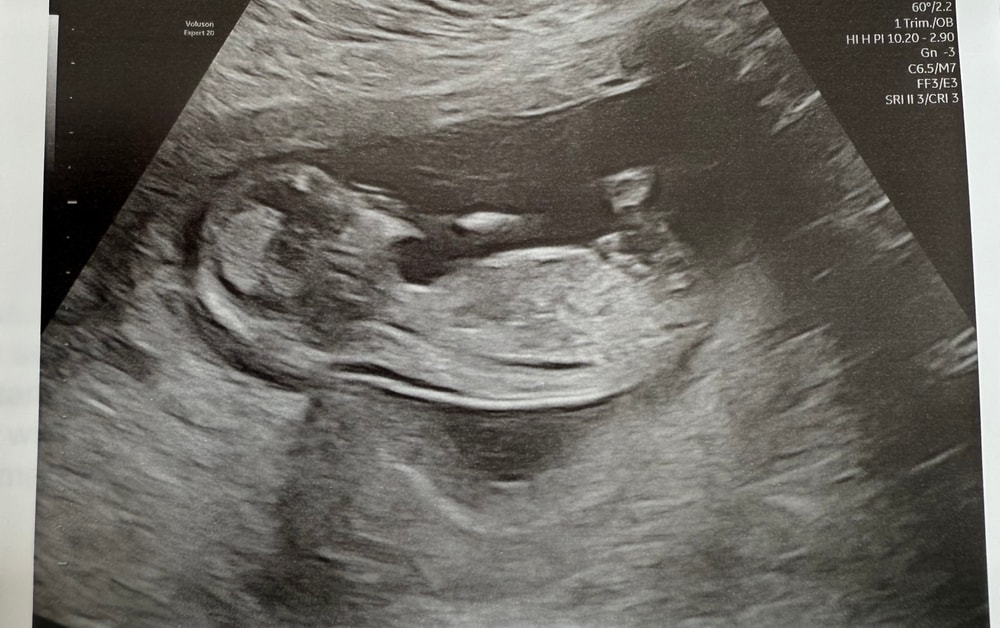

Скрининг 13 н 3 д

Пол малышаНа скрининге врач не предполагала пол, сказала еще рановато. Да и поймать нужный ракурс было трудновато, так как эта креветка постоянно брыкалась😁 поэтому интересно услышать ваше мнение)

P.s. сдавать кровь на определение пола не планирую, да и тут это не практикуется. Просто интересно узнать мнение большинства и после родов сравнить, сбылись ли предположения☺️